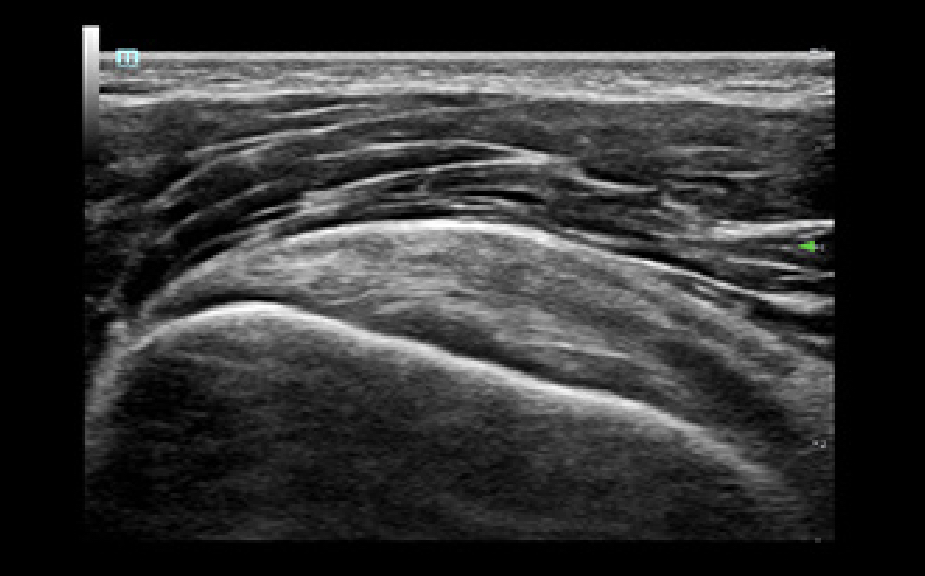

Images

Transducers